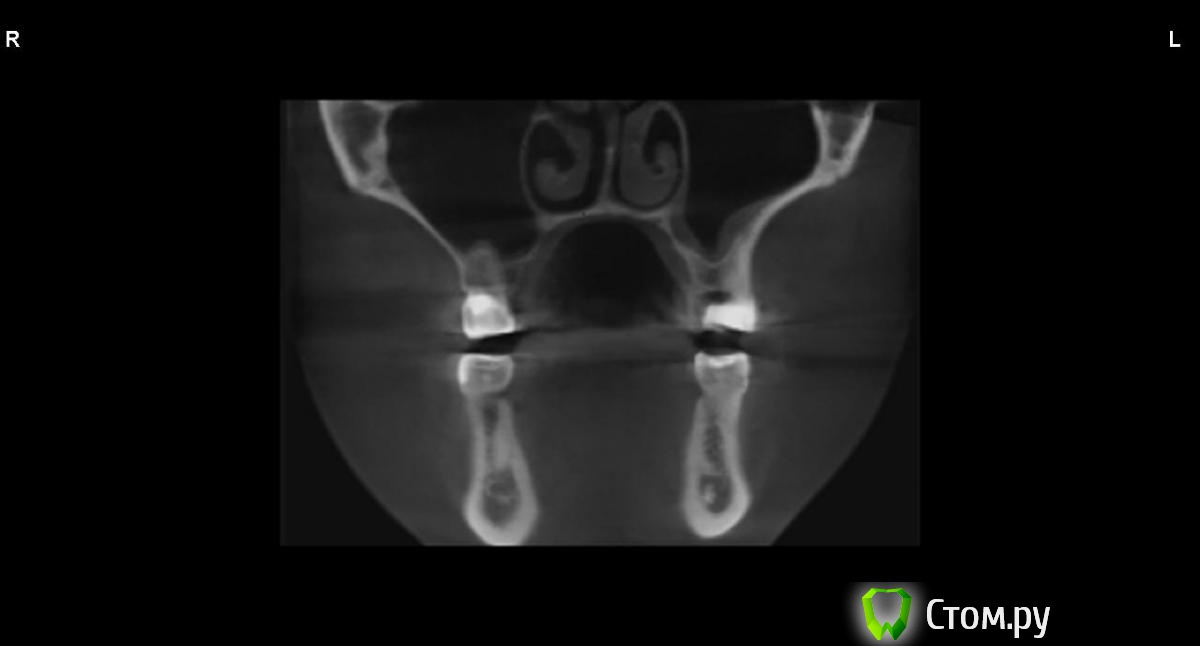

jm3300 Опубликовано 9 сентября, 2014 Автор Поделиться Опубликовано 9 сентября, 2014 вот, набросал Ссылка на комментарий

АнтонТЛТ Опубликовано 9 сентября, 2014 Поделиться Опубликовано 9 сентября, 2014 (изменено) это нижняя носовая раковина, возможно Изменено 9 сентября, 2014 пользователем АнтонТЛТ Ссылка на комментарий

АнтонТЛТ Опубликовано 9 сентября, 2014 Поделиться Опубликовано 9 сентября, 2014 я понял что это)))это артефакт от зуба, обратите внимание на правую сторону, там в пазухе тоже зуб есть, после эндодонтии)) Ссылка на комментарий